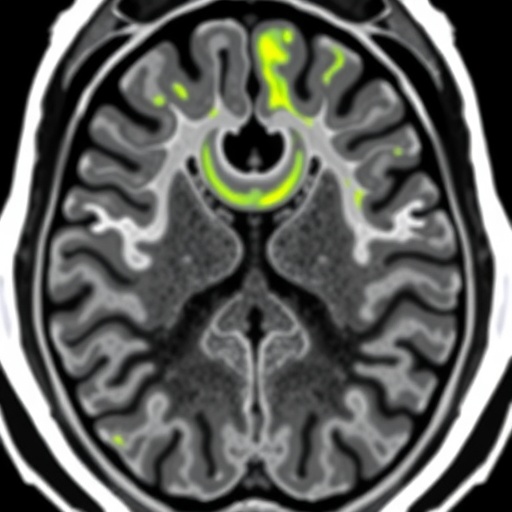

This multicenter, retrospective study compiled data from 206 HCC patients with pathologically confirmed diagnoses, sourced from three distinct hospitals, ensuring a diverse and robust dataset for model training and validation. The investigative team focused sharply on the hepatobiliary phase images (HBP) of gadoxetic acid-enhanced MRI, a specialized imaging sequence known for its superior liver lesion characterization. To harness the full potential of this imaging modality, three variations of deep learning architectures were meticulously developed and assessed: two-dimensional (2D), three-dimensional (3D), and a novel 2.5-dimensional (2.5D) deep multi-instance learning (MIL) model.

Among these approaches, the 2.5D MIL technique emerged as the most potent, ingeniously integrating information from all axial slices encompassing the tumor and surrounding peritumoral regions. This comprehensive slice selection allowed the model to capture both intratumoral heterogeneity and critical peritumoral microenvironmental features, which are hypothesized to play pivotal roles in MVI development. Remarkably, this approach outperformed conventional models with area under the curve (AUC) values reaching 0.802 in internal validation and 0.759 in the external test cohort, highlighting its strong generalizability across patient populations.

Building on these promising findings, the researchers extended their methodology by incorporating additional MRI sequences—T1-weighted fat-suppressed (T1WI-FS) and T2-weighted fat-suppressed (T2WI-FS) images—into a multimodal prediction framework. The synergistic use of these complementary sequences aimed to further refine the predictive algorithm by capturing distinct tissue contrasts and pathological signatures of MVI. This multimodal deep learning model demonstrated exceptional predictive capacity, with AUC values soaring as high as 0.954 in the training set, and sustaining robust performance metrics with AUCs of 0.857 and 0.788 in independent validation and test sets respectively.

These advancements are not merely incremental; they represent a paradigm shift in medical imaging diagnostics for liver cancer. The exploitation of 2.5D MIL in this context signifies a novel computational strategy that leverages the spatial and contextual richness of MRI datasets more effectively than traditional machine learning or purely 2D/3D frameworks. By embracing the heterogeneous nature of tumor microenvironments across consecutive axial slices, this approach unlocks a more nuanced understanding of tumor biology, which is crucial for preoperative risk stratification.

This research also emphasizes the crucial role of peritumoral tissue analysis, an often-overlooked area in conventional imaging assessments. The findings suggest that changes in the tumor microenvironment surrounding hepatocellular carcinoma lesions carry significant predictive information, urging the clinical community to expand diagnostic focus beyond tumor margins. Such insights will likely spur new investigations into tumor-stroma interactions and their implications in cancer progression.